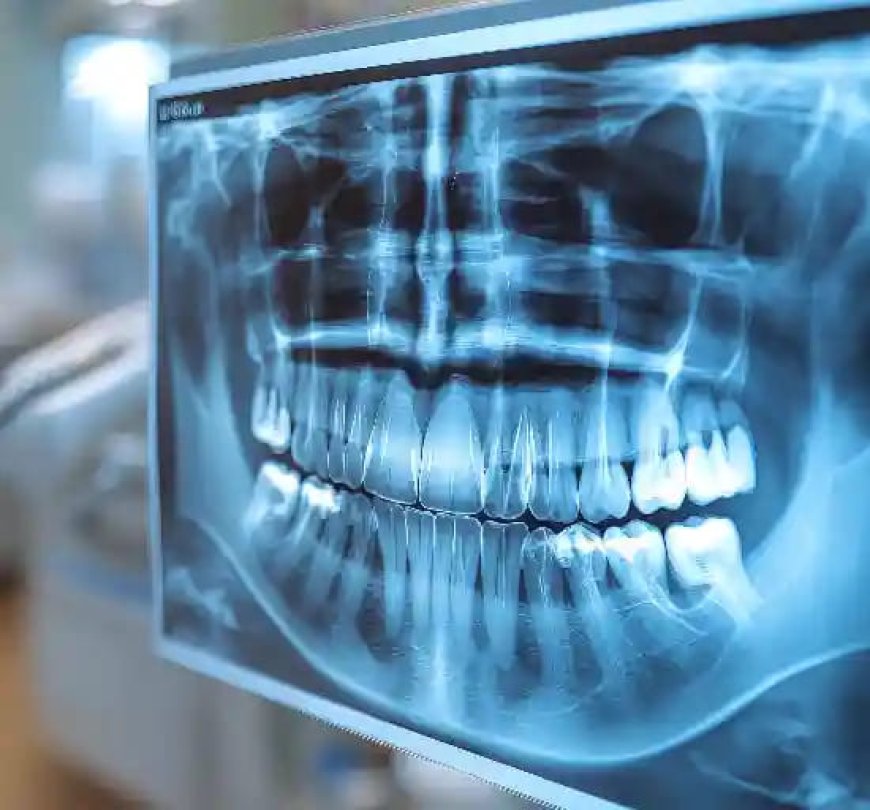

An OPG (Orthopantomogram) scan is a specialized X-ray that provides a panoramic view of your upper jaw, lower jaw, teeth, jawbone, and related structures. Unlike a standard dental X-ray, which takes a small area, an OPG scan images your whole mouth in one picture.

This broad application enables physicians to diagnose matters that are not evident on regular X-rays, and it is thus a useful device in contemporary dentistry and oral medicine.